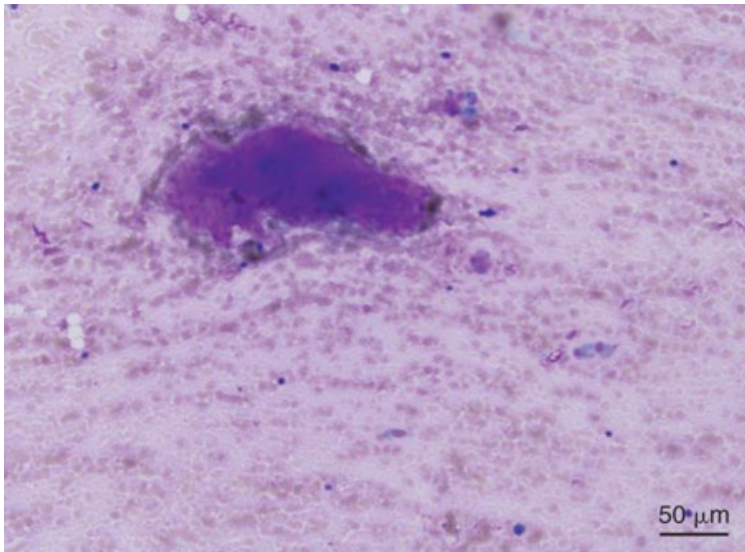

term image

Osteoclast due to articular cartilage erosion in degenerative arthropathy